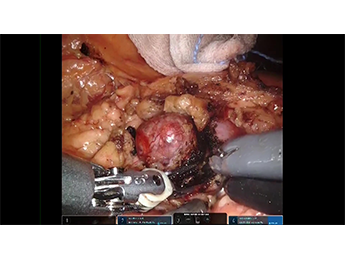

本動画では、腎臓での局所再発症例に対する2回目のRepeat RAPN(ロボット支援下腎部分切除術)について、東京女子医科大学附属足立医療センターの近藤先生にご […]